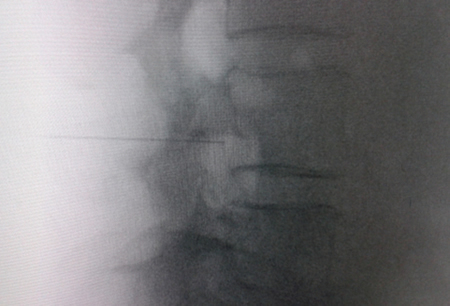

Figure 2